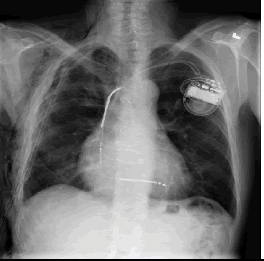

우리에게 굉장히 적은 데이터들이 주어졌을 때, supervised learning을 적용한다면 흔히 overfitting 문제가 발생할 것입니다. 예를 들어, 우리에게 아래와 같은 Chest X-Ray 폐렴 데이터만 갖고 있다고 해보겠습니다.

이미지 출처:https://www.openaccessjournals.com/articles/advanced-neural-network-solution-for-detection-of-lung-pathology-and-foreign-body-on-chest-plain-radiographs-13104.html

그림 출처:https://www.openaccessjournals.com/articles/advanced-neural-network-solution-for-detection-of-lung-pathology-and-foreign-body-on-chest-plain-radiographs-13104.html

의사들이 보는 폐렴 증상은 분명 폐주위의 섬유화에 주목하겠지만, 딥러닝의 경우는 CAM(=Class Activation Map)을 통해 살펴보면 엉뚱한데주목하는 경향이 있습니다. 아래와 같이 엉뚱한 곳을 보는 이유폐렴 관련 데이터는 저런 부분들만 살펴봐도 분류가 가능했기 때문일 수 있습니다. 즉, 정답의 이유는 상관없이 "학습 데이터의 정답만 맞추면 된다"는 식인 것이죠.

하지만, 저런 artifacts와 같은 요소들이 없는 폐렴 데이터가 들어오면 곧 바로 틀려버립니다. 즉, supervsied learning 방식을 사용한 CNN적은 수 의 폐렴 데이터로 학습하게 되면, 폐렴 CXR 이미지를 제대로 representation 해줄 수 없게 된다고 이야기 할 수 있습니다.